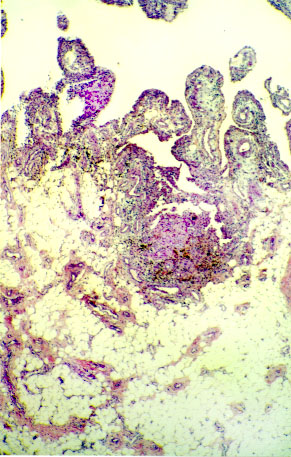

Figura 2.- Estructura vellositaria de la lesión, con ejes fibroadiposos revestidos por epitelio sinovial (H&E 40x).

Figura 3.- Áreas inflamatorias con abundantes siderófagos, responsables del aspecto macroscópico pigmentado de la superficie interna de la lesión (H&E 40x).